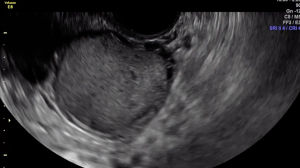

The uterine fundus is being pushed cephalad by the transvaginal ultrasound probe, eliciting smooth sliding of the uterine fundus over the bowel. Some fluid is noted within the rectouterine pouch, which often suggests a non-obliterated pouch.

In this case, there is a fixed ovary posteriorly and subtle hypoechoic nodule posterior to the uterus at the level of the internal cervical os, suggesting of deep endometriosis of the torus uterinus.